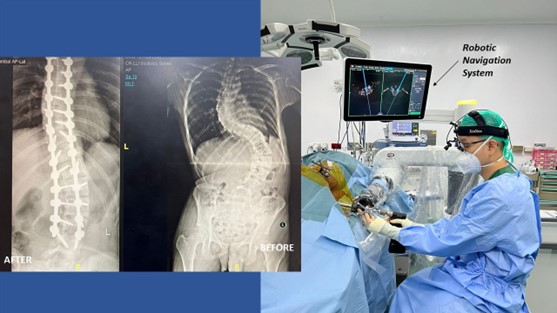

Robot operasi ini disebut hanya ada di Indonesia untuk wilayah se-Asia Tenggara. Teknologi robot navigasi operasi ini digunakan untuk membantu dokter melakukan operasi saraf kejepit, skoliosis derajat ringan hingga kompleks dan yang berhubungan dengan tulang belakang.

"Biasanya operasi menggunakan teknologi robot navigasi tulang belakang ini disarankan untuk jenis saraf kejepit yang membutuhkan pemasangan implant atau bantalan artifisial, sedangkan untuk operasi skoliosis robot navigasi operasi ini membantu saya mengarahkan penempatan implan atau screws secara akurat hingga 99% dan tentunya menghindari terjadinya pendarahan maupun kelumpuhan, sehingga operasi skoliosis menjadi lebih aman," jelas Dokter Rizki Gatam dalam keterangan tertulisnya.